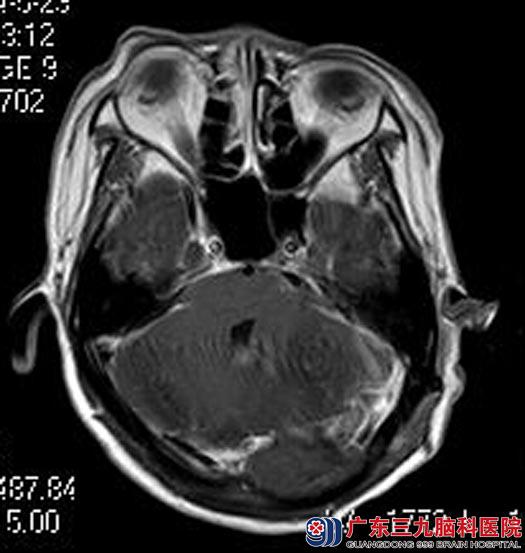

综合神经外科鲁明主任主刀,在全麻下行左侧桥小脑角肿瘤切除术,术中显微镜下探查见桥小脑角粉红色肿物,包膜完整,血运较丰富,肿瘤组织质软,肿瘤与三叉神经、面神经、粘连,予逐步分离切除,完整保留三叉神经、面神经,过程顺利。术后,小清左侧面部抽搐完全消失,耳鸣症状明显好转。术后病理结果:过渡型脑膜瘤。

手术后